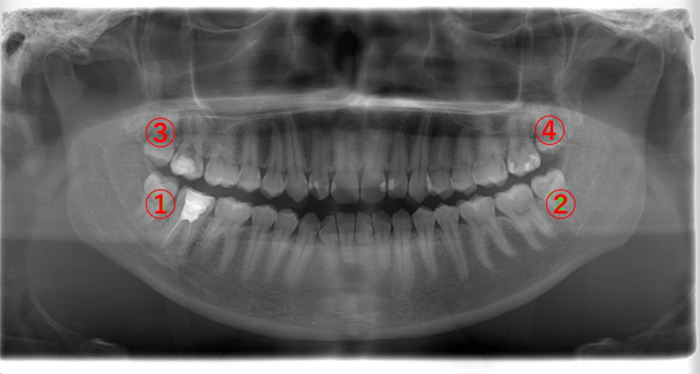

(24歳女性)

| 年齢・性別 | 24歳・女性 |

|---|---|

| 主訴 | 右上の親知らず(画像③)が急に痛み始めた。 |

| 歯ブラシ | 毎日歯を磨いている。 親知らずまでは磨けてない。 |

画像③の親知らずを見てみると黒く透けています。虫歯になると歯が溶けて柔らかくなるので、レントゲンでは黒く写ります。虫歯が歯の神経に達すると痛みが強くなります。

③の親知らずを抜歯して、①の親知らずも抜きたいところですが、③の親知らずの痛みが強いこともあり、一緒に抜歯せずに後で③の親知らずを抜く方が良いと説明しました。

親知らず以外の歯に関してはかなりきれいに磨けていました。奥にある親知らずの歯ブラシが難しいことがわかります。

痛みが強い歯は、その状態により対合する歯を一緒に抜くことができないこともあります。